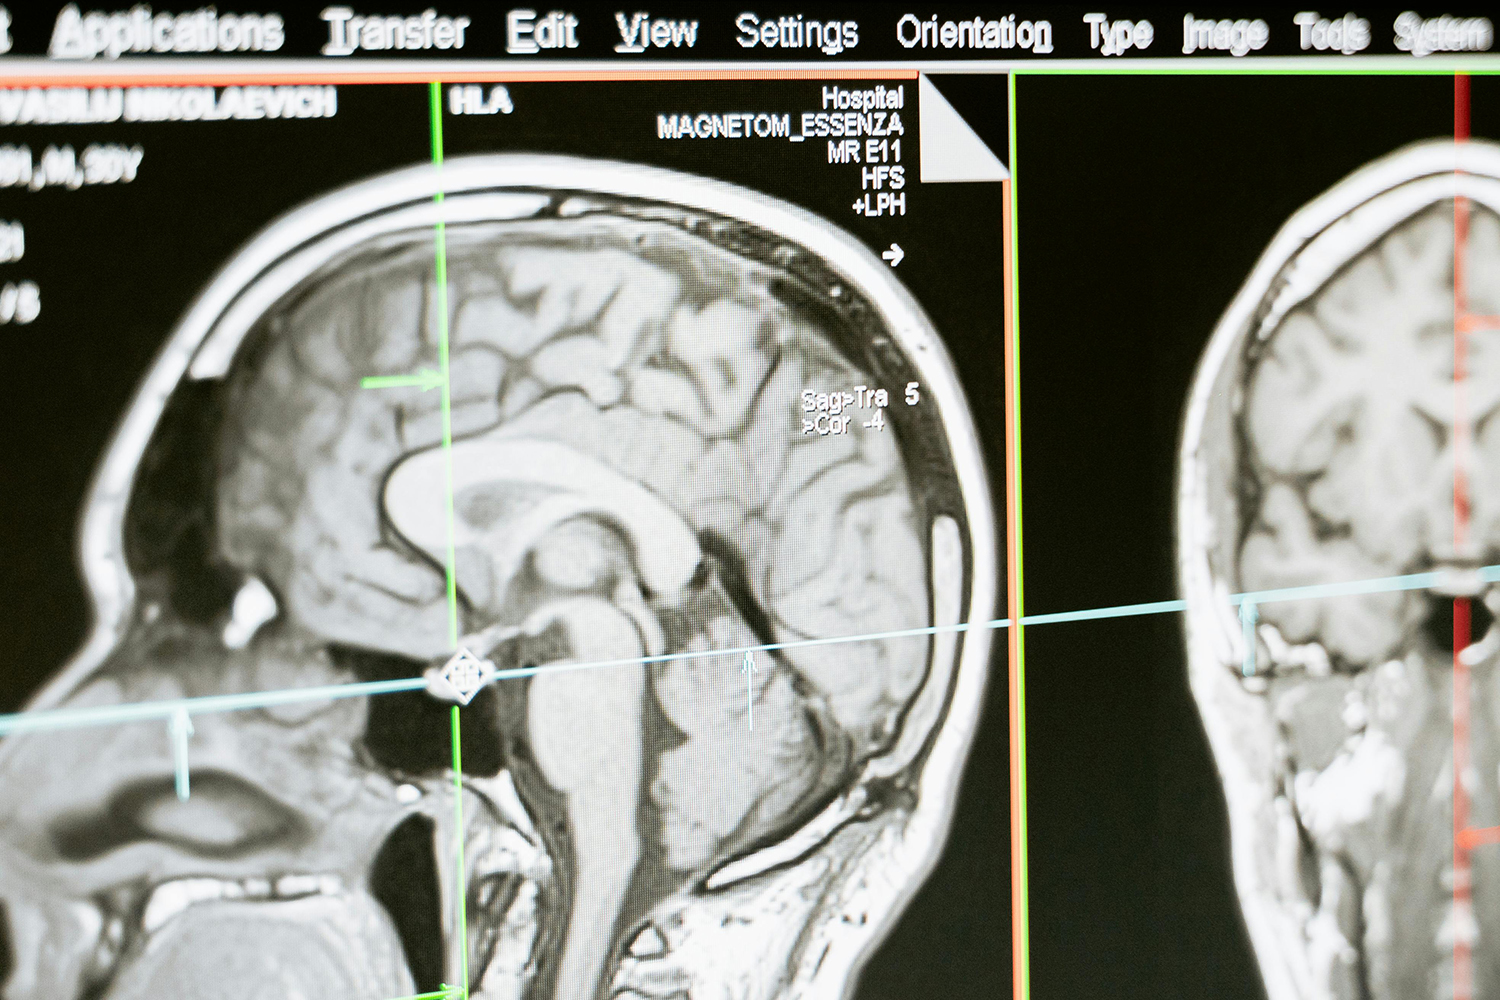

核磁共振成像(MRI)目前普遍應(yīng)用于醫(yī)學(xué)檢測(cè)成像中,具有無(wú)輻射損傷的安全性,可任意方位斷層掃描等技術(shù)靈活性,加以涵蓋質(zhì)子密度、弛豫、加權(quán)成像以及多參數(shù)特征的優(yōu)勢(shì),已成為當(dāng)代臨床診斷中最有力的檢測(cè)手段之一,然而臨床發(fā)現(xiàn)某些不同組織或腫瘤組織的弛豫時(shí)間相互重疊,導(dǎo)致診斷困難。